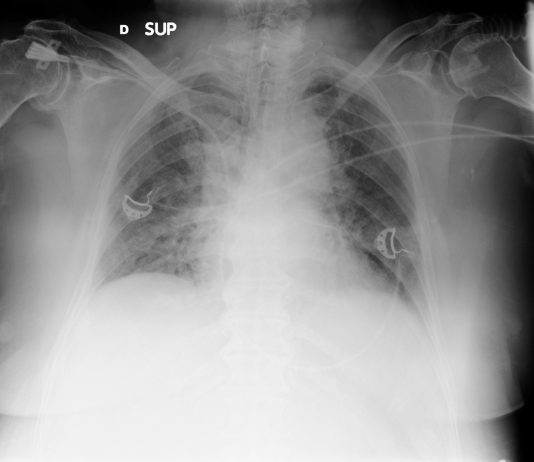

46-year-old asymptomatic female patient underwent chest radiography followed by CT since her husband was diagnosed of Covid-19 pneumonia (case n 14). pO2: 98%.

Chest radiography